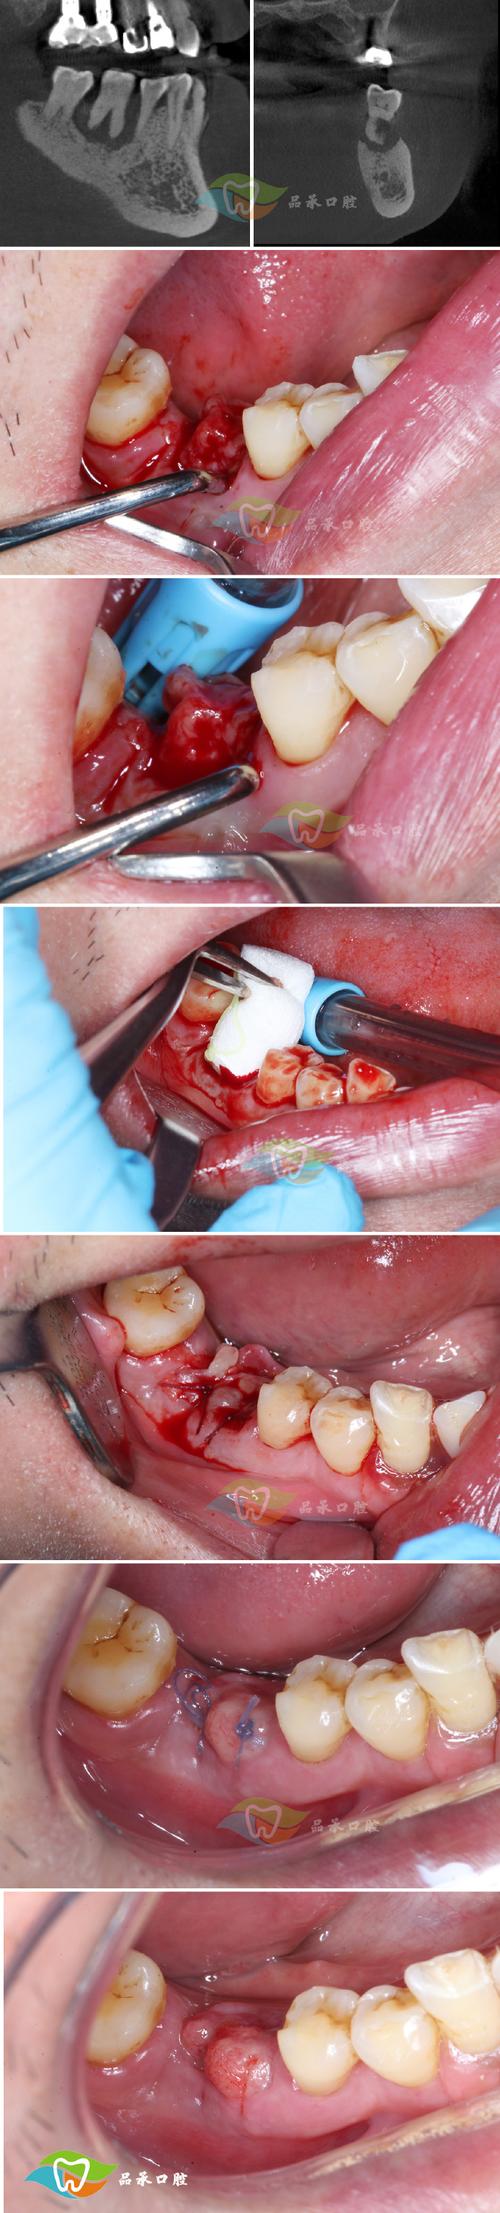

缝合步骤(以间断缝合为例)

- 定位: 确定第一针的位置(通常从颊侧或舌侧龈缘开始)。

- 进针: 针持夹住缝线针的中后1/3处,针尖垂直于牙龈表面,在游离龈缘(靠近牙面处)刺入,深度约2-3mm(穿过黏膜下层,到达骨膜表面),避免刺入骨组织或过深进入肌肉。

- 穿出: 针在骨膜上约1-2mm处穿出。

- 对侧进针: 将针移动到对侧(舌侧或颊侧)对应的龈缘位置,同样垂直刺入骨膜,从龈缘穿出。

- 打结:

- 保持缝线适度张力(不要过紧导致组织缺血坏死,也不要过松导致创口裂开)。

- 使用外科结(先打两个单结,再打一个双结,或三个单结),确保打结牢固,打结时缝线需在垂直方向拉紧,避免滑脱。

- 结的位置应在牙龈乳头处(两牙之间的牙龈),避免直接压在拔牙窝内或骨缘上。

- 重复: 根据拔牙窝大小和形态,在颊舌向或近远中向再缝合1-3针,覆盖整个拔牙窝,确保所有撕裂的牙龈都被复位缝合。

- 剪线: 用线剪在靠近打结处剪断缝线,线尾保留约1-2mm。

- 检查: 再次检查缝合情况:

- 创口是否完全关闭,无死腔。

- 牙龈边缘是否对合整齐,无内卷或外翻。

- 缝线松紧是否适度。

- 无缝线残留或异物。